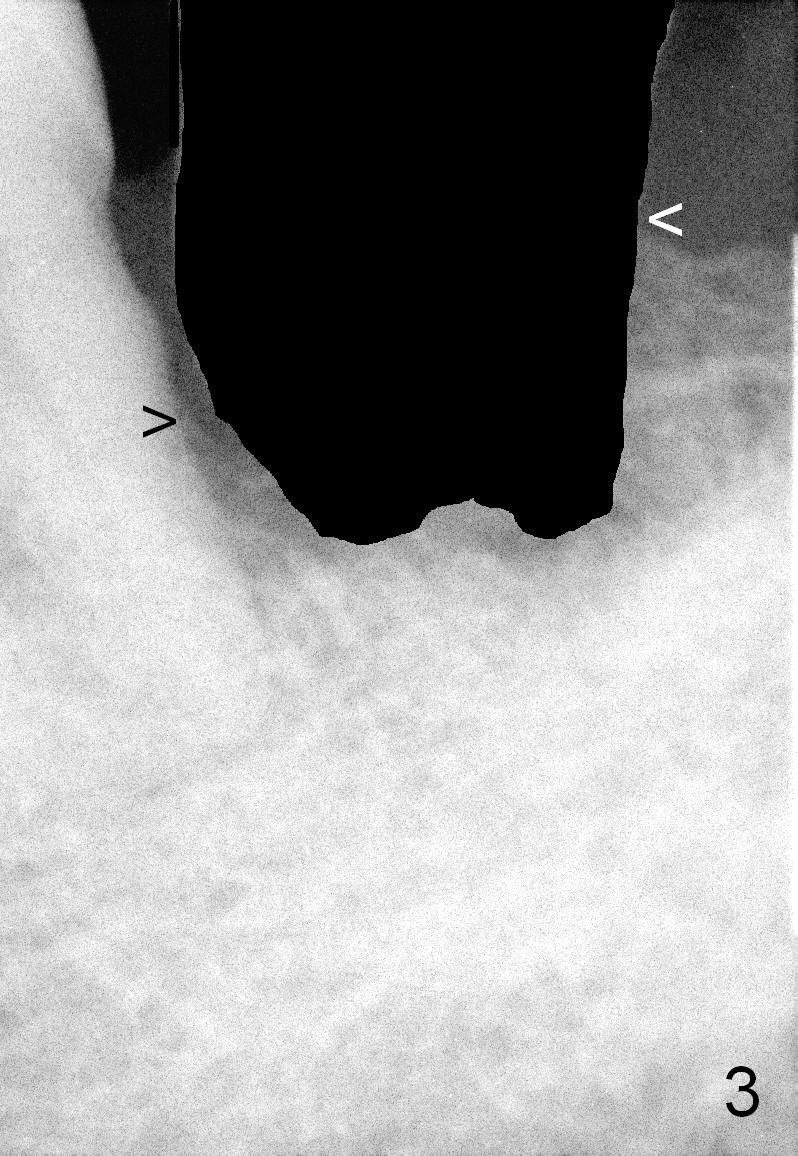

A 63-year-old man has periodontitis. The tooth #18 (probably 17) has mobility III (Fig.1). Three more PAs are taken with deeper placement of #2 sensor (Fig.2,6,7) to show the upper border of the Inferior Alveolar Canal (yellow dashed lines). The affected tooth has severe bone loss, especially mesially (Fig.2,3 (arrowheads)). No matter whether bone (Fig.4) or gingiva (Fig.5)-level implant is placed, the threads should be covered circumferentially by bone, native or grafted (red circles). In Fig.5, the threads are apical to black arrowheads, whereas the rough surface, which should be also contacted by bone, is the lower half above the black arrowheads.